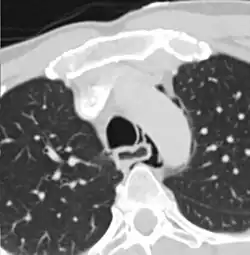

Tomografia com sinais compatíveis com ruptura esofagiana.

A Síndrome de Boerhaave é a ruptura espontânea do esôfago, ocorre subitamente e gera risco de morte. Em 80% dos casos é precedida por episódios de vômitos intensos. Descrita pela primeira vez por Hermann Boerhaave.